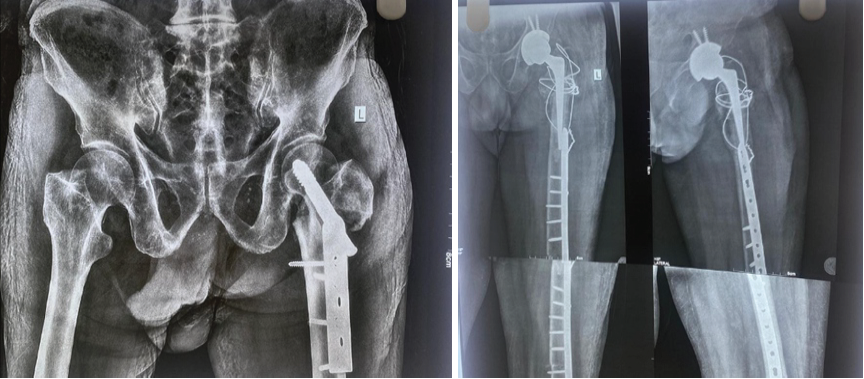

Figure 2: Case 2- Diagnosis: Failed valgus osteotomy post-fracture neck of femur with deformity. Procedure: Hybrid total hip arthroplasty with derotation osteotomy and augmentation plate.

Another patient had an intraoperative dislocation, and an immediate derotation osteotomy of the distal femur was performed due to poor bone stock with plates and screws (Fig. 3). Mobilization was as follows: Six patients were mobilized on post-operative day 1; three patients had to be placed in a derotation boot for 4 weeks, two patients were advised non-weight bearing ambulation until further advice. Post-operative follow-ups were conducted at 1, 3, 6, and 12 weeks, and annually for up to 2 years.

Primary THA has been proven to be effective in managing failed fracture fixation of the hip [1,6,9]. Failure modes such as osteonecrosis, screw cutout, and hardware loosening necessitate revision strategies that often involve extensive reconstruction [2]. Modern cemented and uncemented implants offer excellent long-term survival [3]. Proper pre-operative planning and radiographs are mandatory for adequate planning and implant selection. Augmentation materials such as Prolene mesh and cerclage wiring facilitate stability in deficient bone stock [8]. In our study, the usage of augmentation devices in appropriate cases proved higher functional outcomes and faster recovery in daily living. The usage of Prolene mesh (Fig. 2) for reconstruction of abductor deficiency has yielded excellent outcomes when compared to previous studies [8]. The addition of plates and screws (Fig. 3) has also yielded lower rates of failure and dislocation [2,5]. Ethibond sutures for soft-tissue reconstruction have been used in a few cases for severe soft-tissue damage due to previous surgeries and have not been described commonly in old literature. Younger patients with adequate bone stock benefit from uncemented THA(Fig 4,Fig 5), whereas cemented options are better suited for elderly or osteoporotic patients [5]. Adequate counseling is essential regarding potential risks, including dislocation, infection, and prolonged rehabilitation [4,10].